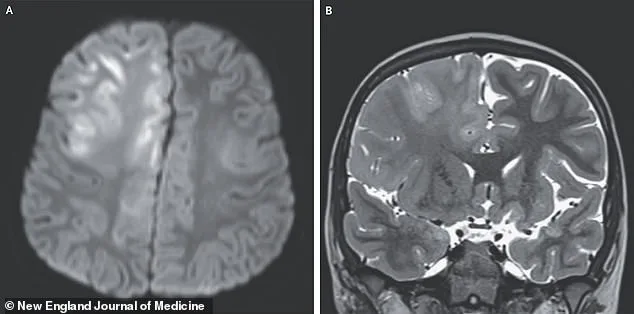

The boy's medical journey was harrowing. By age seven, he began experiencing seizures and a progressive loss of cognitive abilities. His reflexes became hyperactive, spasming uncontrollably, and he lost the ability to speak. An MRI revealed alarming signs: swelling in the brain's frontal lobe and corpus callosum, with slowed water molecule movement—a clear indicator of cellular damage. Doctors diagnosed him with SSPE, a rare neurological disorder that develops in about one in 1,000 measles cases. This condition, which has a 95% mortality rate, claimed the boy's life a year after symptoms first appeared, as detailed in the *New England Journal of Medicine*.